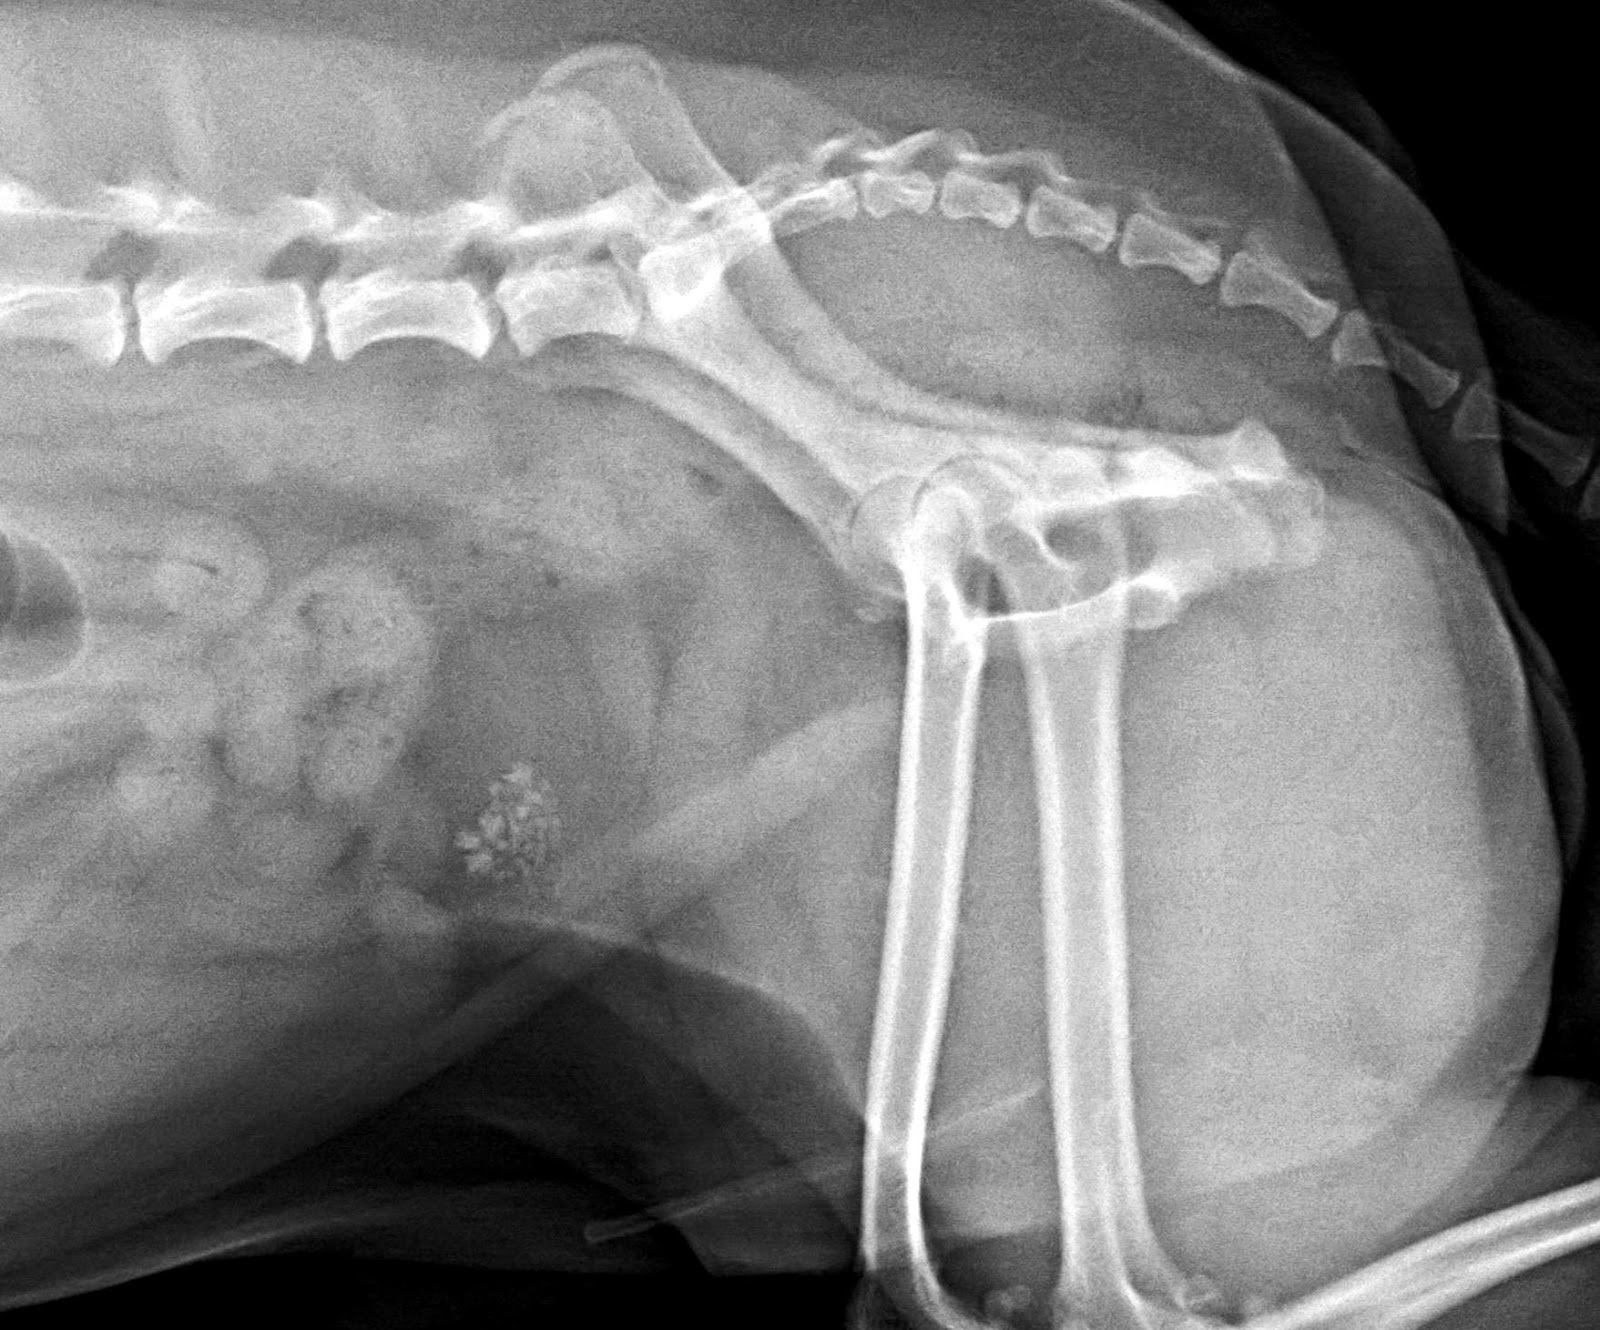

Radiopaque Urinary Stones Dog . These smooth to slightly rough, relatively large radiopaque. Cystine (hexagonal) crystals are pathognomonic for cystinuria, but crystalluria is absent in many. Not all uroliths are radiopaque; Straining to urinate (called dysuria). They are correct that urate and. The most common signs of bladder stones in dogs are: Therefore, it is recommended that diagnostic imaging consist of abdominal radiography (to include the urethra). Canine struvite / calcium phosphate carbonate. These radiopaque stones are similar to calcium oxalate, but are more common in dogs with hypercalcemia. Radiopaque stones include struvite and calcium oxalate. Blood in the urine (called hematuria) and. Don’t be fooled by published texts describing urate and cystine uroliths as radiolucent. Stones vary from radiographically invisible to mildly radiopaque.

They are correct that urate and. The most common signs of bladder stones in dogs are: Therefore, it is recommended that diagnostic imaging consist of abdominal radiography (to include the urethra). Don’t be fooled by published texts describing urate and cystine uroliths as radiolucent. Canine struvite / calcium phosphate carbonate. These radiopaque stones are similar to calcium oxalate, but are more common in dogs with hypercalcemia. These smooth to slightly rough, relatively large radiopaque. Radiopaque stones include struvite and calcium oxalate. Not all uroliths are radiopaque; Stones vary from radiographically invisible to mildly radiopaque.

Radiopaque Urinary Stones Dog The most common signs of bladder stones in dogs are: Don’t be fooled by published texts describing urate and cystine uroliths as radiolucent. Therefore, it is recommended that diagnostic imaging consist of abdominal radiography (to include the urethra). Straining to urinate (called dysuria). The most common signs of bladder stones in dogs are: These smooth to slightly rough, relatively large radiopaque. Not all uroliths are radiopaque; Cystine (hexagonal) crystals are pathognomonic for cystinuria, but crystalluria is absent in many. Stones vary from radiographically invisible to mildly radiopaque. Blood in the urine (called hematuria) and. Radiopaque stones include struvite and calcium oxalate. They are correct that urate and. Canine struvite / calcium phosphate carbonate. These radiopaque stones are similar to calcium oxalate, but are more common in dogs with hypercalcemia.